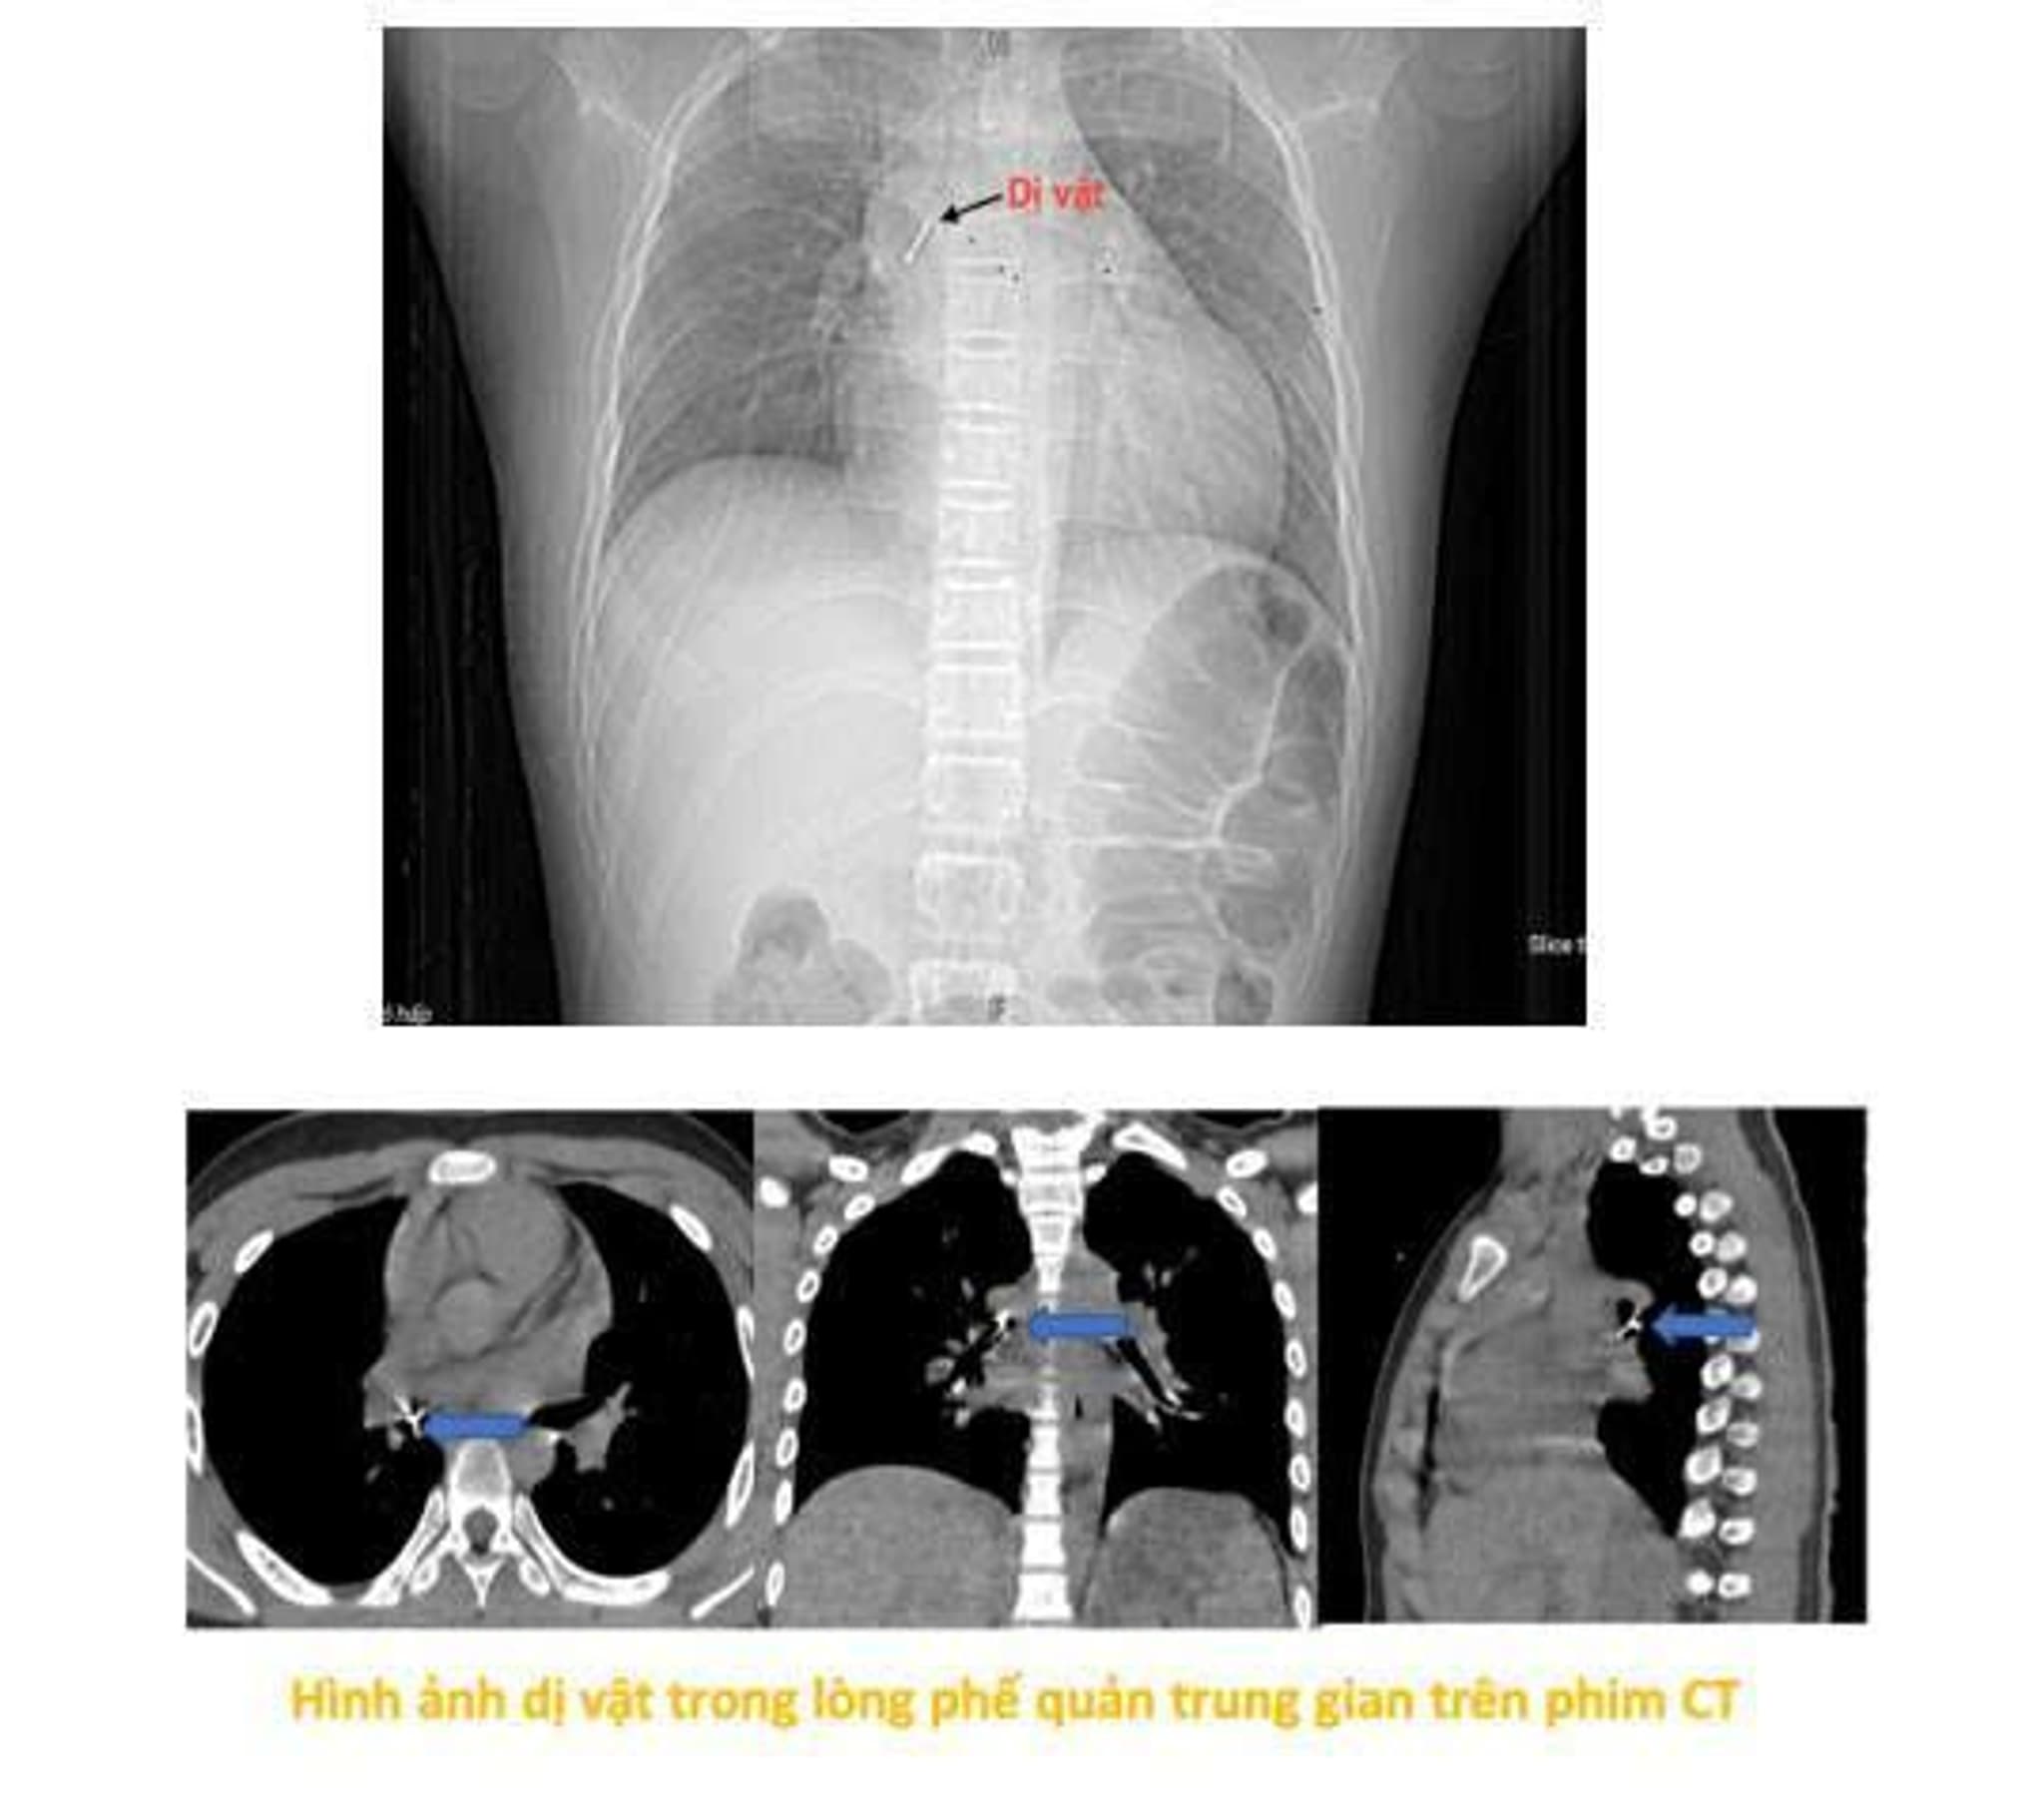

Theo gia đình, tối ngày 13/10/2025, bé P. vừa ngồi xem điện thoại vừa ngậm chiếc đinh ghim bảng dài khoảng 2,5 cm. Trong lúc cười lớn, chiếc đinh bất ngờ rơi vào họng khiến bé ho sặc sụa, khó thở và cảm giác vướng ở ngực, nói khó. Gia đình hốt hoảng đưa trẻ tới Bệnh viện gần nhà. Tại đây, bệnh nhi được làm các xét nghiệm máu, chụp phim cắt lớp vi tính lồng ngực, nội soi phế quản ống mềm, các bác sĩ xác định dị vật đã nằm sâu trong phế quản trung gian bên phải. Do dị vật sắc nhọn, đâm xuyên thành phế quản gây chảy máu và phù nề niêm mạc nên việc gắp gặp rất nhiều khó khăn. Sau hơn 2 giờ thực hiện thủ thuật không thành công, bệnh nhi được chuyển khẩn cấp sang Bệnh viện Phổi Trung ương.

Tiếp nhận ca bệnh, ThS.BSCKII Nguyễn Lê Nhật Minh – Trưởng khoa Nội soi chẩn đoán và can thiệp cùng ê-kíp đã nhanh chóng tiến hành thủ thuật nội soi phế quản ống mềm gắp dị vật để xử trí. “Dị vật là chiếc đinh ghim sắc nhọn, nằm vướng tại phế quản trung gian, đầu nhọn đâm xuyên sâu vào thành phế quản. Đây là ca gắp dị vật rất khó, bởi ngoài tính chất, đặc điểm của dị vật như trên, bệnh nhi còn phản ứng theo phản xạ nên cần đòi hỏi thao tác nhanh, chính xác tuyệt đối để tránh làm rách thành phế quản hay đẩy dị vật xuống sâu hơn, có thể dẫn tới nhiễm trùng, chảy máu, tràn khí màng phổi, tràn khí trung thất. Thậm chí những biến chứng đó có thể gây hậu quả suy hô hấp cấp cho người bệnh. Do vậy sau khi đã đánh giá toàn diện kíp thực hiện đã cẩn trọng gỡ phần đầu đinh đang cắm vào thành phế quản thành trạng thái tự do bằng những dụng cụ kìm nội soi phế quản chuyên dụng, rồi từ từ gắp thành công dị vật ra ngoài. Quá trình diễn ra trong vòng 15 phút.” bác sĩ Minh cho biết.